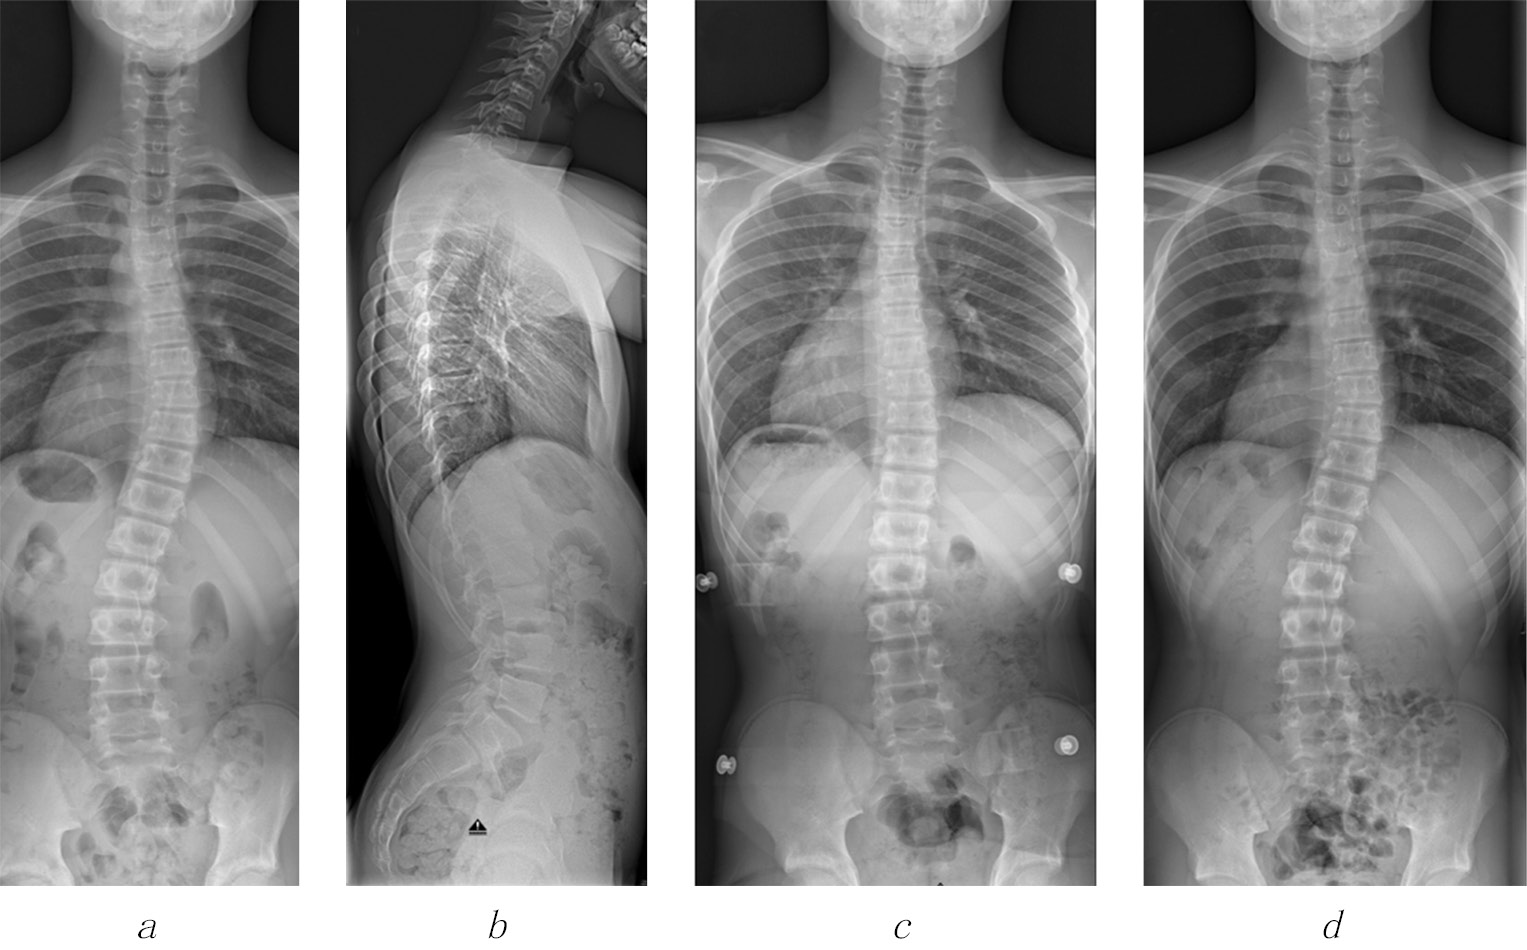

After approval of the institutional ethical review committee of the University Medical Center, a cohort of 52 AIS patients from a single medical university center, which were treated conservatively with a Chêneau brace therapy were followed from the beginning of treatment until the end of growth and several months (average nine months) after brace therapy. According to Richards et al. [15] SRS (scoliosis research society) paper on brace studies, inclusion criteria at the beginning of brace treatment were the diagnosis of AIS, minimum age of ten years, Risser sign 0 to 2 (<50% ossification of the iliac apophysis on radiographs), scoliotic curve angle (Cobb degree) between 25° and 40°, less than one year after the menarche and no prior treatment. Patients who satisfied these criteria and who were treated with a Chêneau brace until the end of skeletal growth (Risser sign 5), were included into this study. Additionally, 14 patients with a scoliotic curve angle of 17°–24° were included as brace therapy is suggested at 20° of scoliosis in Germany and a measurement error of 5° should be considered using the Cobb method. Clinical data such as curve patterns and body mass index were documented. Standardized radiological standing images in the AP (anterior-posterior) and lateral projections at the first visit were performed and analyzed. In order to reduce radiation exposure, follow-up radiographs were performed as an AP standing film only (Fig. 1).

Fig. 1. A 12-year old boy with scoliosis (a) and a normal sagittal profile (b). Scoliosis could be well corrected by a Chêneau brace (c). At six months follow-up after the end of brace treatment, spinal deformity was similar to the initial values (d)

All patients were prescribed a Chêneau brace, which were manufactured at different companies throughout the country. After completion of the brace, a period of adjustment was recommended with increasing wear duration. If necessary, an adaptation of the orthosis was performed by the manufacturing company. An outpatient visit was scheduled three to five months after the initial visit to check on the brace and to perform AP radiographs in the brace to proof deformity correction. All adolescents and their parents were instructed to wear the brace for 23 hours/day [14] and only to take it off during sports and showers. Physiotherapy was prescribed with a given preference to the Schroth method to de-rotate, stabilize and elongate the spine in a three-dimensional plane [16]. Objective data on real brace time wearing and physiotherapy effors were not collected. Therefore, the reported data represent a typical everyday situation in a large pediatric spine clinic.